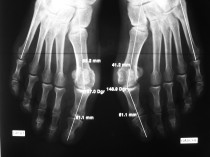

Dans ce cadre, je vous propose un large spectre des techniques de diagnostic et de traitement: consultation spécialisée, explorations complémentaires et interventions chirurgicales.

Vous pouvez également me poser des questions par mail sur des cas particuliers, si possible accompagnés d'imagerie car cette chirurgie repose pour beaucoup sur ces documents, mais il ne s'agira que d'un avis consultatif théorique, car rien ne remplacera l'information personnalisée obtenue auprès du médecin après consultation et examen clinique.